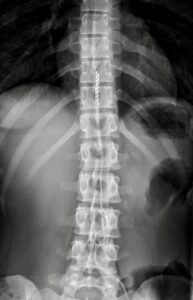

Medullary Neurostimulation or Spinal Cord Stimulation allows through percutaneous implantable systems such as electrodes and pulse generator (pacemaker), to create an electromagnetic field around the spinal cord, capable of interfering with the conduction of chronic neuropathic pain.